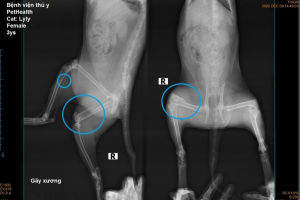

X-quang ổ bụng chó mèo tại Sing Pet Biên Hòa, Đồng Nai. Chẩn đoán nhanh, chính xác, phát hiện dị vật, tắc nghẽn, u ổ bụng, hỗ trợ điều trị và theo dõi hậu kiểm hiệu quả.

X-quang ổ bụng là phương pháp chẩn đoán hình ảnh sử dụng tia X để quan sát các cơ quan bên trong ổ bụng của chó, mèo, bao gồm dạ dày, ruột, gan, thận, bàng quang và các cấu trúc xung quanh.

Tại Bệnh viện Thú Y Sing Pet Đồng Nai, dịch vụ X-Quang Ổ Bụng Cho Thú Cưng Biên Hòa giúp phát hiện các bệnh lý, dị vật, tắc nghẽn, u hoặc các vấn đề tiêu hóa một cách nhanh chóng và chính xác.

Hiển thị cấu trúc các cơ quan ổ bụng, phát hiện dị vật, khối u hoặc tắc nghẽn.

4.3. X-quang toàn thân

Đánh giá phối hợp giữa ổ bụng và xương khớp, đặc biệt khi chó mèo bị chấn thương đa hệ thống.